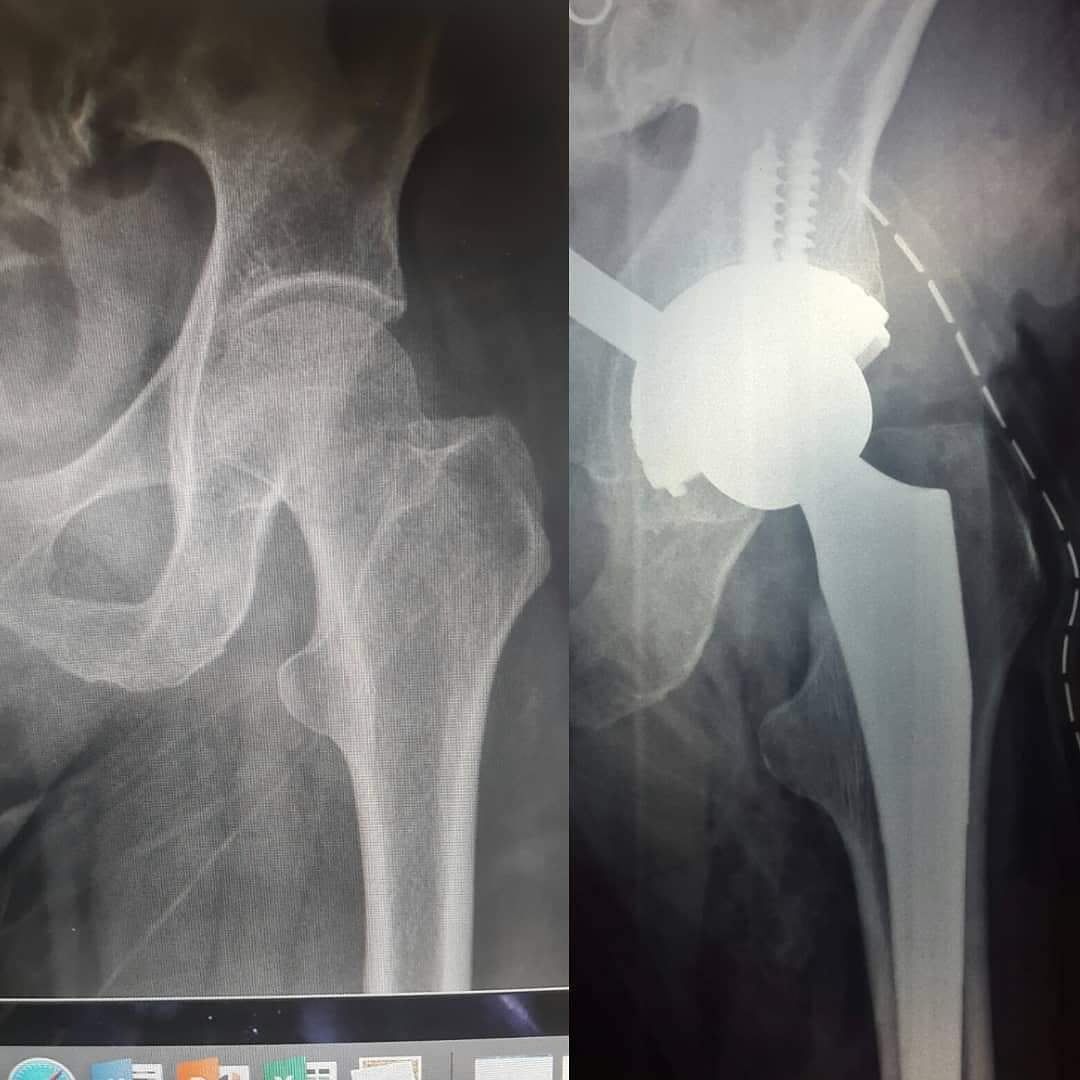

Querido paciente, soy Traumatólogo y Ortopedista egresado del Hospital Central de la Universidad Autónoma de San Luis Potosí, donde me especialicé a tratar todo tipo de problemas en el sistema musculoesqueletico, desgaste, fracturas, luxaciones, lesiones ligamentarias de (hombro, codo, mano, muñeca, columna, cadera, rodilla, pie y tobillo)

Tuve la oportunidad de estar en "Centre Hospitalier de Dax - Côte d'Argent" en FRANCIA, donde aprendí a utilizar los mejores y más novedosos materiales para tratar todo lo relacionado a fracturas, columna y artroscopia.

• Fracturas de cadera

• Fractura de fémur

Artroplastia de la cadera con prótesis total